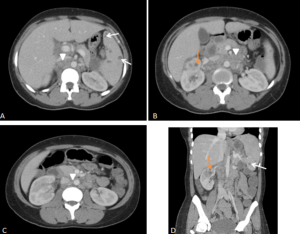

RPF typically appears as a well-defined, irregular paraspinal soft-tissue mass, isodense to the psoas muscle and without lateral extension beyond it. Most often centred at L4–L5 near the aortic bifurcation, it may extend cranially towards the renal hila or, less commonly, caudally to involve pelvic structures. Baseline Hounsfield units (HU) values and the diameter of the retroperitoneal tissue can assist in assessing inflammatory activity. [1,3,5-8]